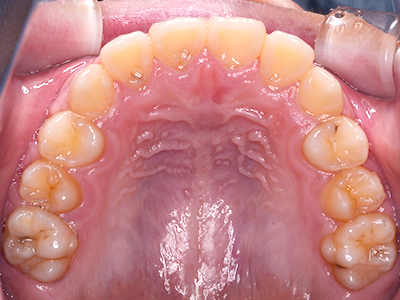

矯正装置を装着し、調整しながら少しずつ歯を移動させ、歯並びを整えていきます。

状態によって家庭でのトレーニングが必要な場合もあり、治療期間も個人差があります。

あくまでも平均値ではありますが、一般的には月1回程度来院頂き、1~2年程度を目安に治療を進めていきます。